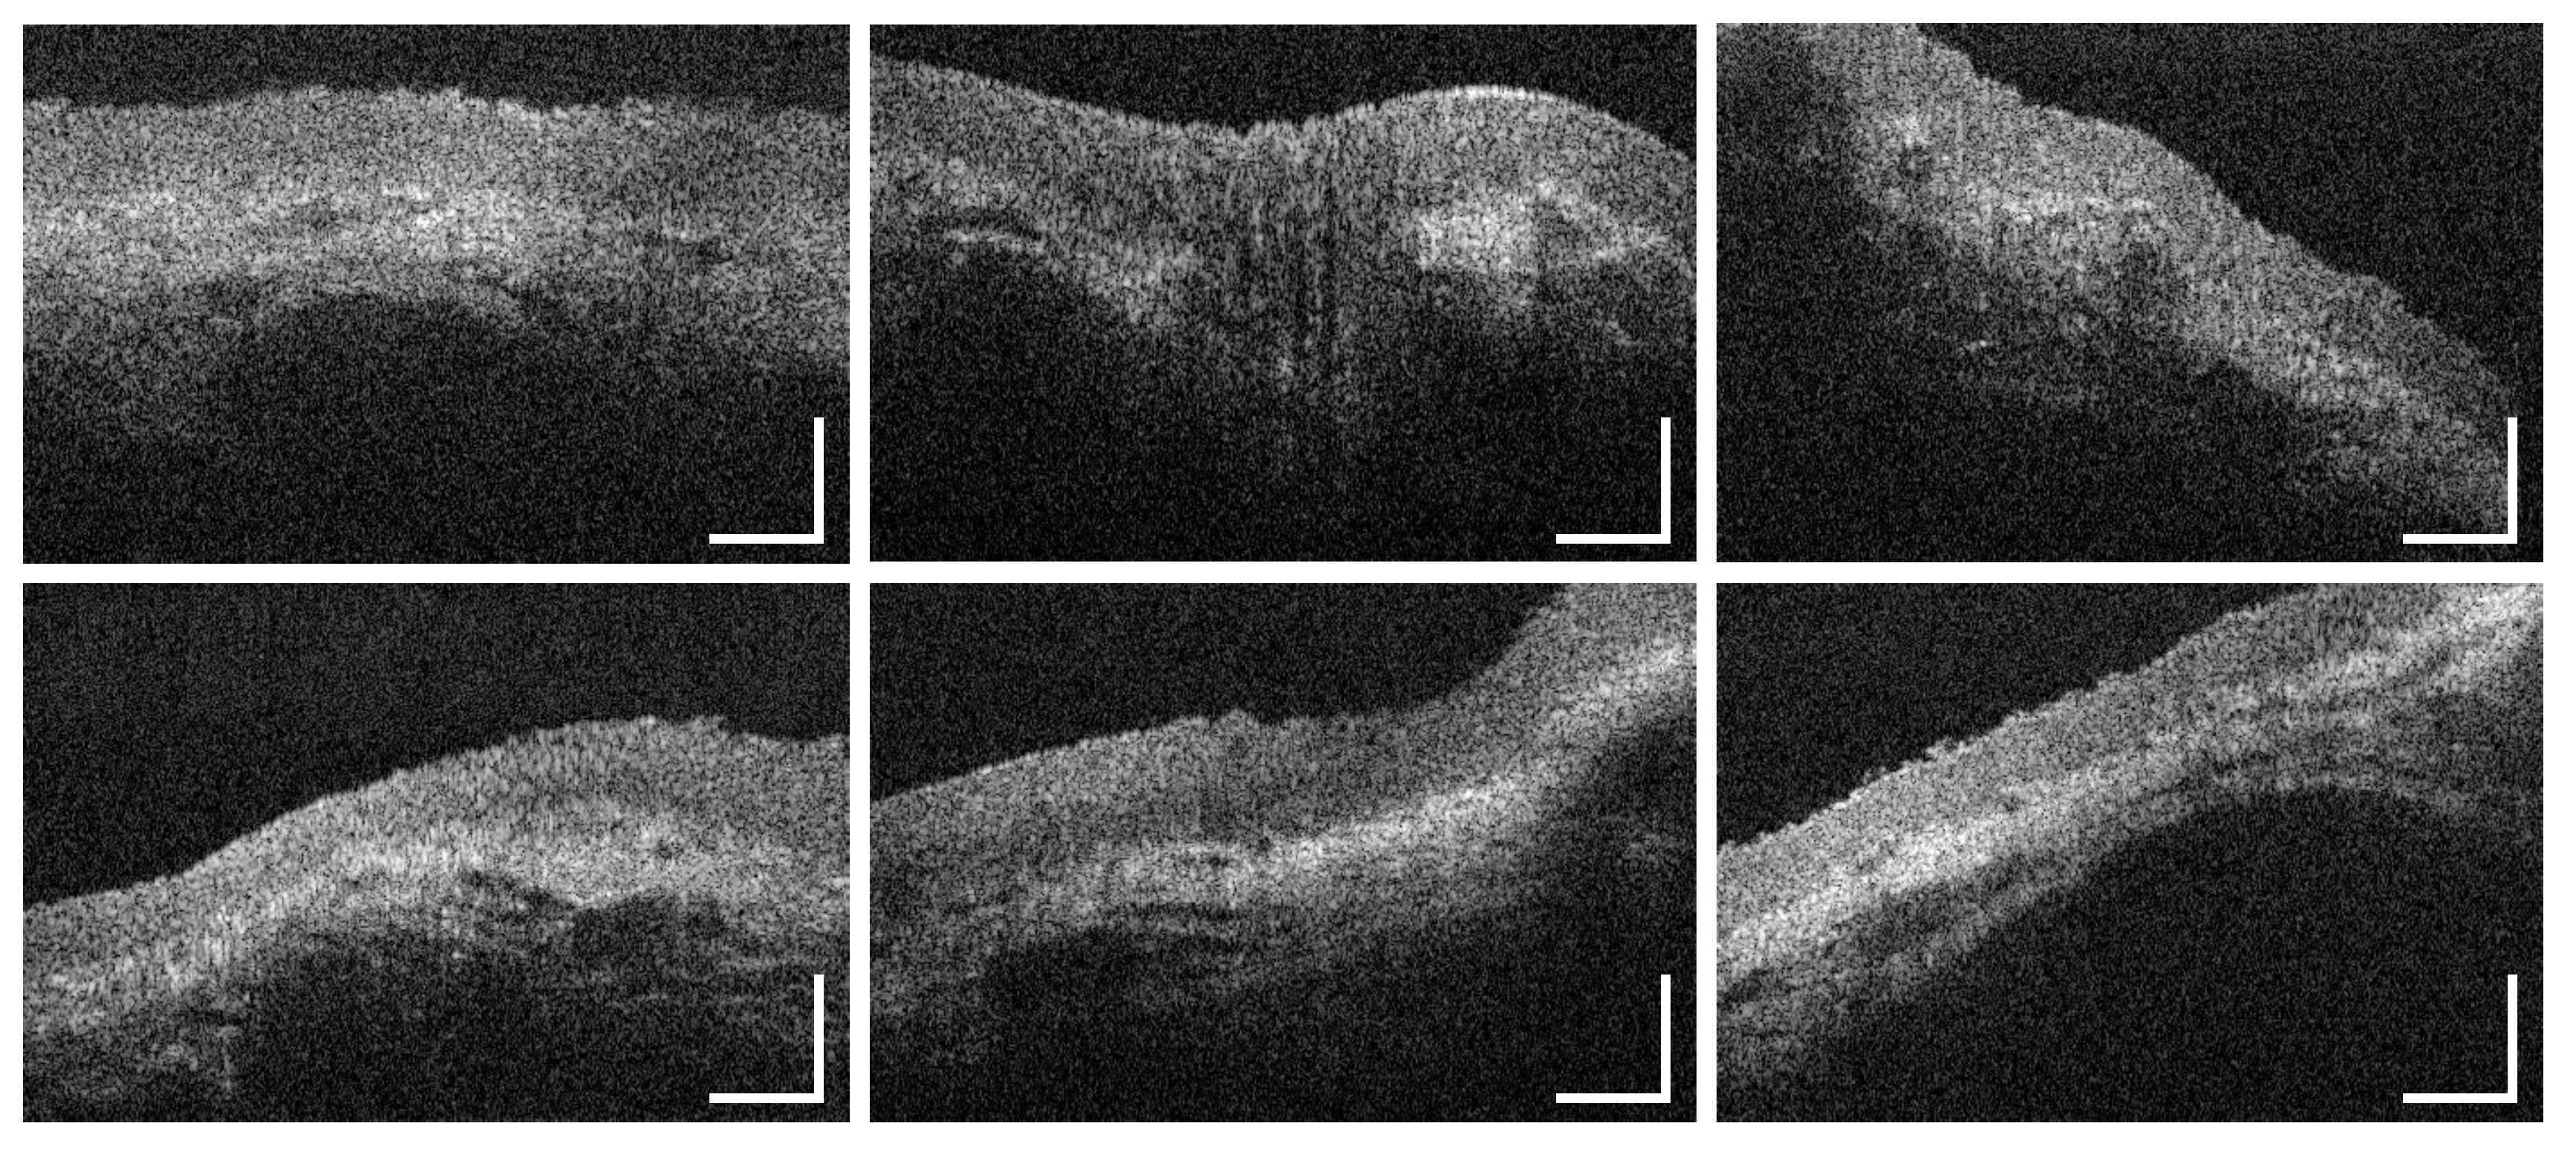

3.1. Labial and Alveolar Mucosa

3.2. Buccal Mucosa

3.3. Sublingual Mucosa

3.4. Hard Palate

3.5. Soft Palate and Oropharynx

3.6. Palatine Tonsils